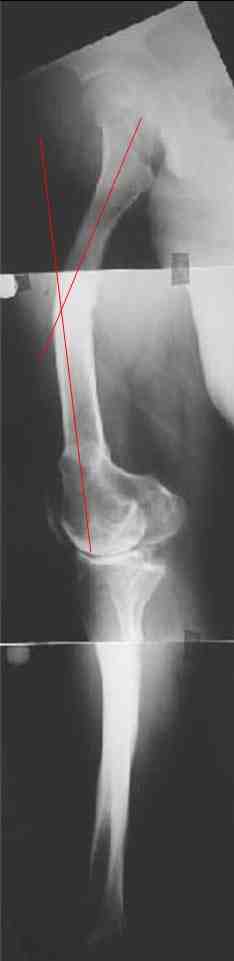

В данном случае перед эндопротезированием мы бы корригировали оси бедренной и большеберцовой костей (см. вложение). Дистальный эпидиафизарный угол бедра будет корригирован при эндопротезировании. Тип остеотомии и коррекции деформации (клиновидная резекция - одномоментная коррекция; формироване треугольных или трапециевидных регенератов во времени) - исходя из

относительной длины конечности.

На бедре дистальный отдел в сгибательной установке после, видимо, когда-то сделанной корригирующей остеотомии. Не надо ли на том же уровне все-таки "разогнуть" бедро до протезирования? Сам протез, наверно, можно поставить в большем или меньшем "сгибании", но весь дистальный эпиметафиз бедра и все нижележащее оказывается кзади от механической оси бедра. Насколько это допустимо, не ведет ли к расшатыванию протеза? Или можно как-то рассчитать такой наклон протеза, что он компенсирует это смещение?

И нет ли смысла аппаратом исправить не только кривые диафизы, но и взимоотношения собственно суставных концов бедренной и большеберцовой костей, они ведь там контактируют с вальгусом градусов 25? Это позволит дозированно удлинить мягкие ткани по латеральной стороне.

Это один из самых сложных вариантов для эндопротезирования, т.к. мы имеем деформацию бедренной кости в трех проекция, думаю, что есть и

ротационная деформация, плюс к этому - деформация голени. Однозначно в таких случаях, в отличии от возможностей при эндопротезировании ТБС необходимо выполнить корригирующие остетомии на двух уровнях. Что касается сгибательно установки мыщелков бедра - думаю, что это не является проблемой, особенно если на операции будет испрользован заднестабилизированный протез. Относительно вальгуса - все не так однозначно - возможно, что деформация слегка преувеличена за счет проекционной установки из-за ротационной деформации. Поэтому планирование операции необходимо будет делать только после коррекции деформации.